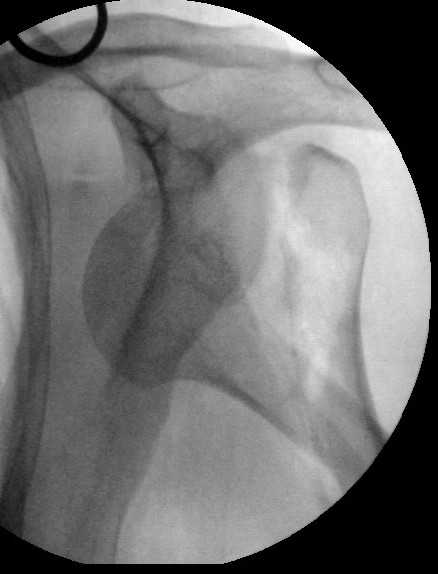

Попытка закрыто изменить положение не удалась. Передним доступом сделали открытую репозицию, гленоид без особенностей. Временно фиксировали спицами и остроконечным костедержателем. Фиксировали гвоздем T2 PHN (Stryker). Для профилактики вывихов после введения проксимальных винтов ротировали дистальный отдел кнаружи на 30

градусов как аналог остеотомии по Weber. Снимки в приложении. Комментарии и критика привествуются.

Attempt of closed reduction failed. Open reduction via anterior approach. The head was temporarily fixed by wires and sharp clamps. Fixation by a nail - T2 PHN (Stryker). The distal fragment has been rotated 30 degrees externally after proximal locking for dislocation prevention as "virtual" Weber osteotomy. Images attached.

Comments/critics are welcome.